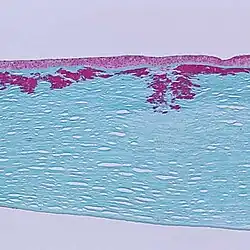

This gene encodes an RGD-containing protein that binds to type I, II and IV collagens. The RGD motif is found in many extracellular matrix proteins modulating cell adhesion and serves as a ligand recognition sequence for several integrins. This protein plays a role in cell-collagen interactions and may be involved in endochondrial bone formation in cartilage. The protein is induced by transforming growth factor-beta and acts to inhibit cell adhesion.[5]